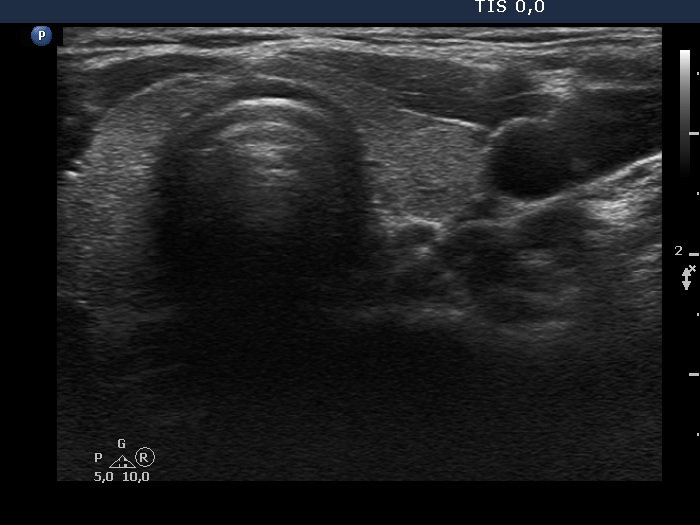

Discrete lesion or nodule in Hashimoto's thyroiditis - case 26 (1048)

Second examination three years later (ultrasonographic picture 5)

Left lobe, transverse scan.